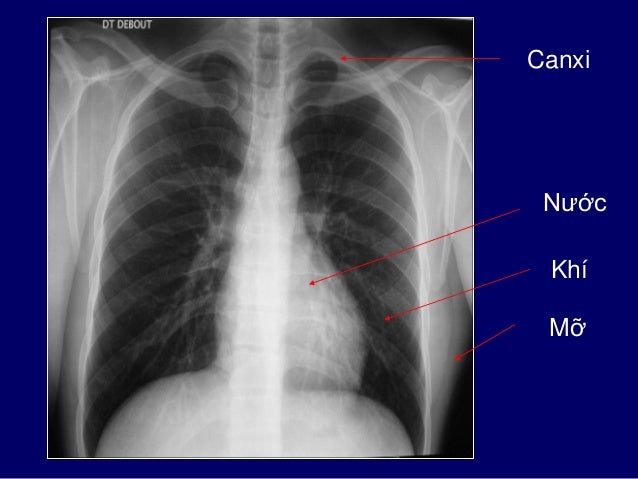

15. 15. QUI ƯỚC ĐỘ CẢN TIA TRÊN XQ Canxi Nước Mỡ Khí

16. 16. Canxi Nước Khí Mỡ